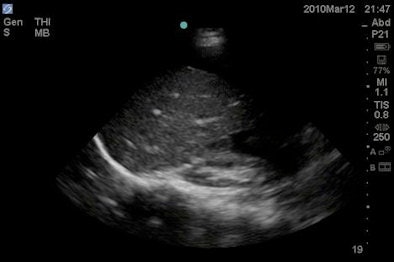

Emergency medicine attending physicians were surveyed after an initial clinical evaluation of the patient, and goal-directed ultrasound was then performed using a M-Turbo compact-ultrasound scanner (SonoSite) by credentialed emergency sonologists not directly involved with patient care.

A standard ultrasound protocol for hypotension was employed, including a cardiac study (encompassing ejection fraction estimation, right ventricular [RV] dilation, and the presence or absence of pericardial effusion and tamponade), inferior vena cava (IVC) diameter measurement, a FAST (focused assessment with sonography for trauma) exam, an aorta scan (to check for abdominal aortic aneurysm), and a thoracic study (to detect pneumothorax).

In other findings, Shokoohi reported that ultrasound found abnormal IVC diameter in 46% of patients, abnormal ejection fraction in 36%, RV dilation in 14%, peritoneal and pleural free fluid in 13%, pericardial effusion in 8%, tamponade in 1.4%, and abdominal aortic aneurysm in 1.4%. No pneumothorax cases were found.